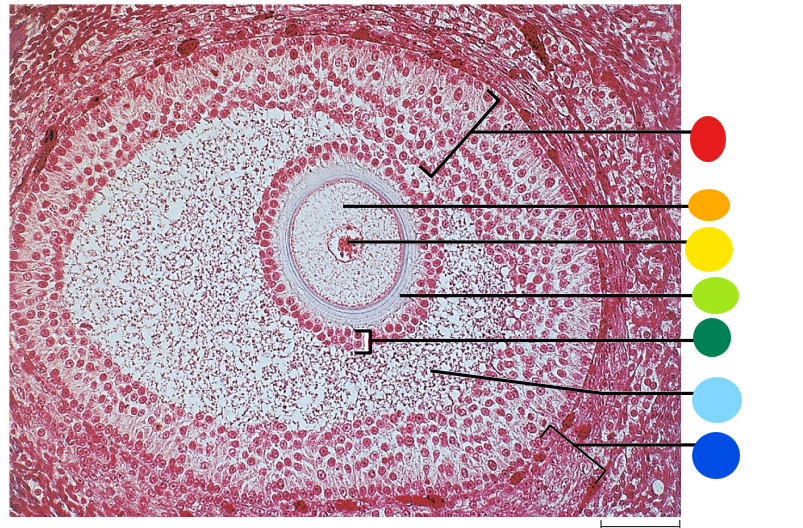

red

primordial follicles

red

primary follicles

red

tunica albuginea

orange

primary oocyte

yellow

primordial follicles